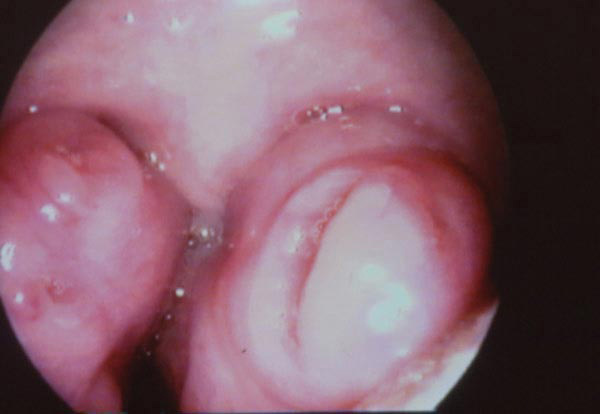

Les amygdales sont hypertrophiées et obstructives, en dehors de toute signe d’angine. Cette hypertrophie peut provoquer une obstruction des voies aériennes.